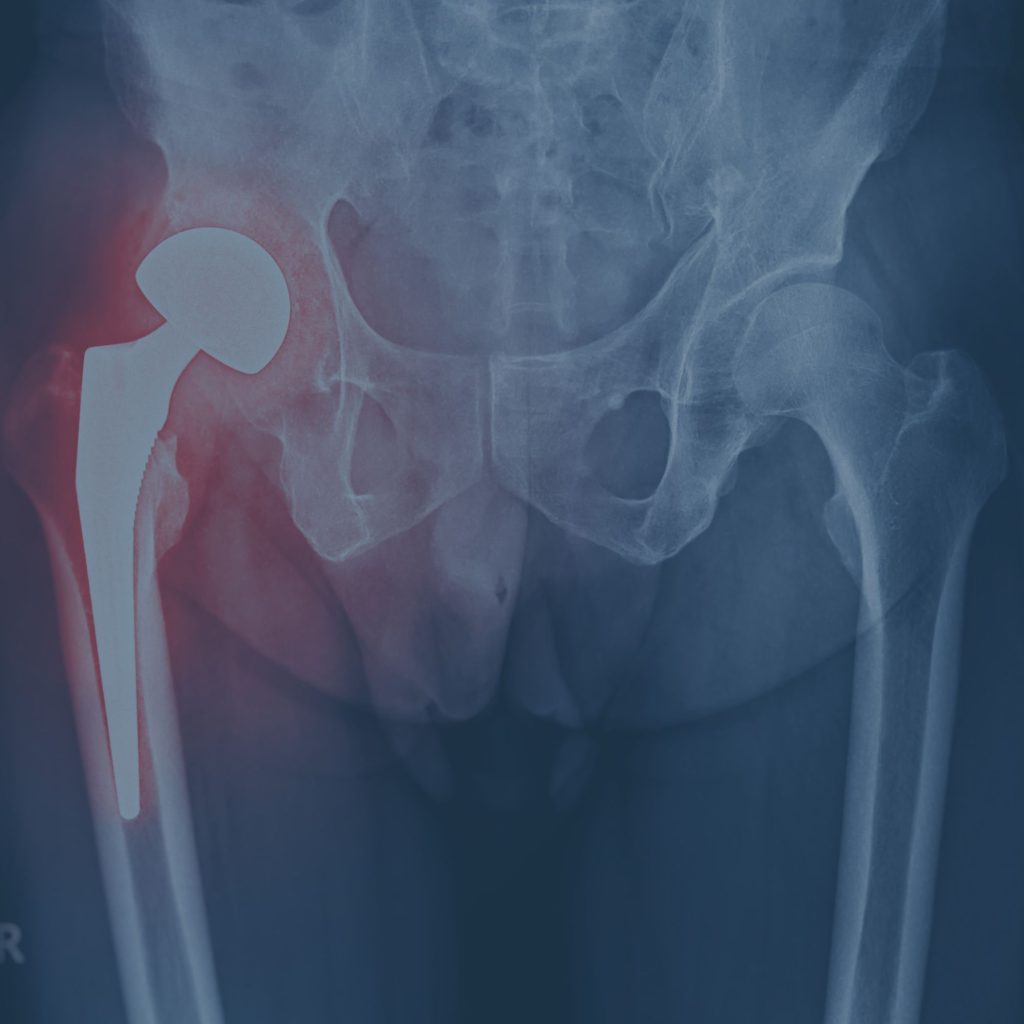

Anca

Camminare, salire le scale e persino dormire possono essere alcune delle attività quotidiane in cui un problema all'anca può condizionare la vita di una persona. Condizioni come l'artrosi dell'anca, il conflitto femoro-acetabolare, la necrosi della testa del femore o esiti di traumi, possono compromettere significativamente la mobilità e la qualità della vita, rendendo ogni movimento una fonte di dolore e limitazione.

Anca

Camminare, salire le scale e persino dormire possono essere alcune delle attività quotidiane in cui un problema all'anca può condizionare la vita di una persona. Condizioni come l'artrosi dell'anca, il conflitto femoro-acetabolare, la necrosi della testa del femore o esiti di traumi, possono compromettere significativamente la mobilità e la qualità della vita, rendendo ogni movimento una fonte di dolore e limitazione.